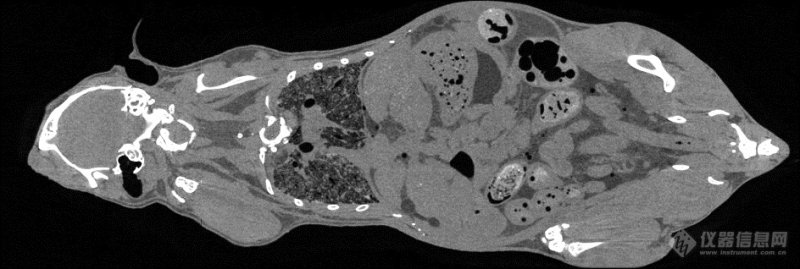

鼠全身成像(中科院高能所 供图)